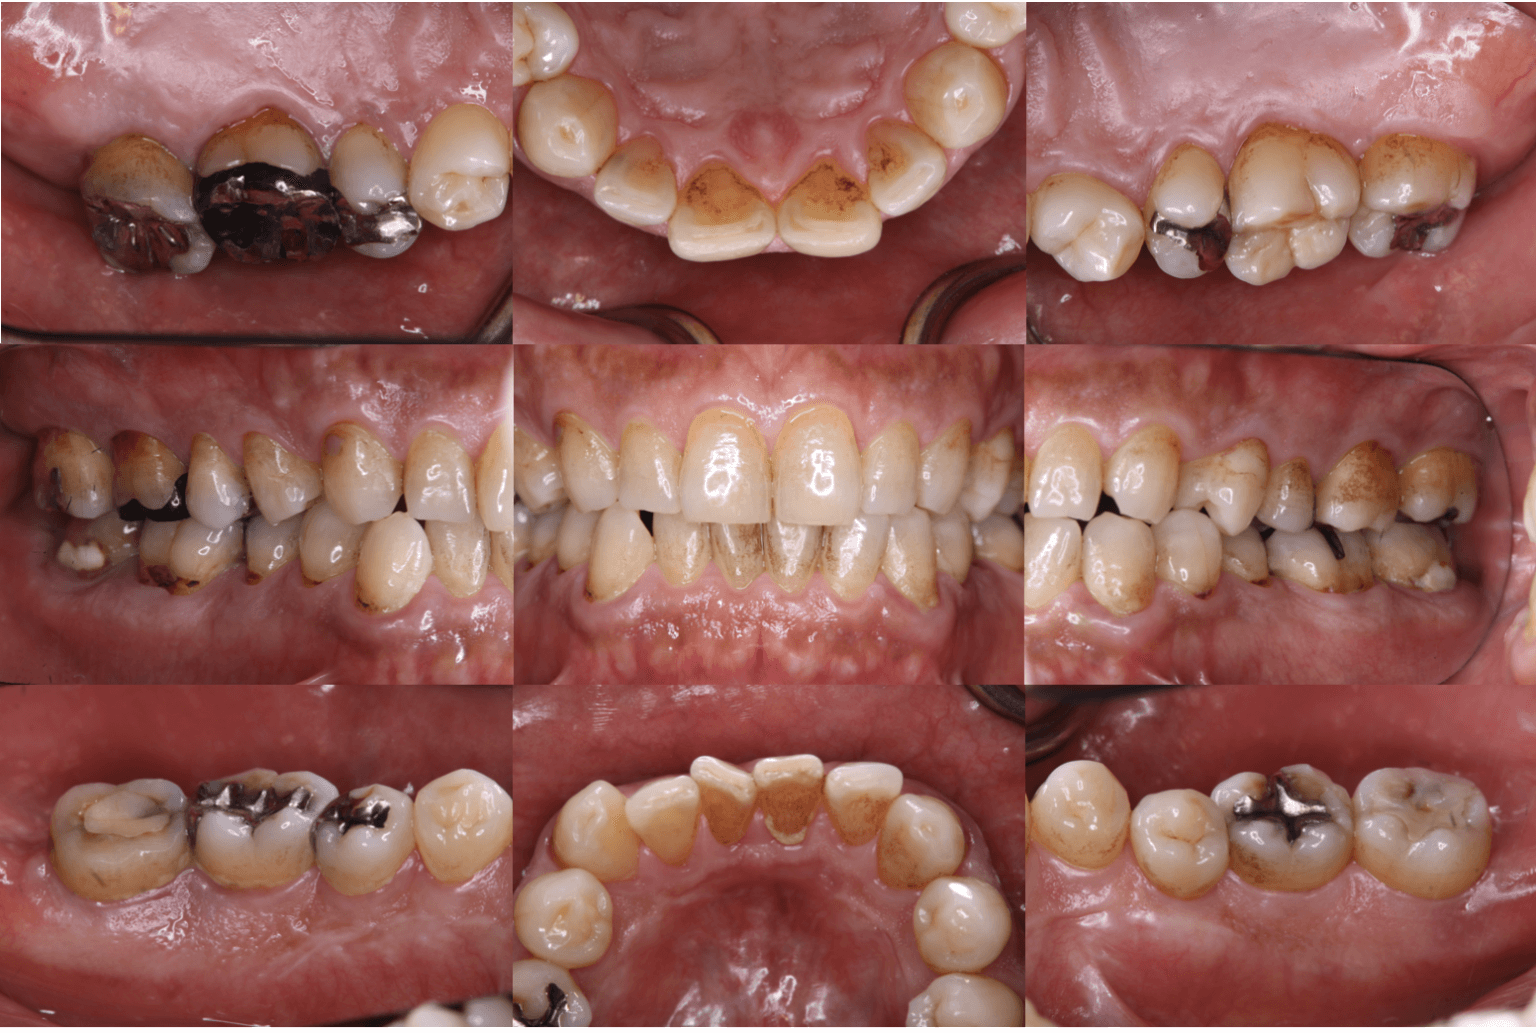

④口の中の写真

この検査は、治療の進行状況や口腔内の状態を詳しく記録するために非常に役立ちます。写真は治療の検査でとても重要です。治療を始める前に、歯や歯ぐきの状態を写真に記録することにより、治療の効果を比較することができます。そして、写真をもとに、どの部分に重点的な治療が必要かを確認し、最適な治療計画を立てます。そして定期的に写真を撮ることで、治療の効果や進行状況を確認し、必要に応じて治療計画を調整します。